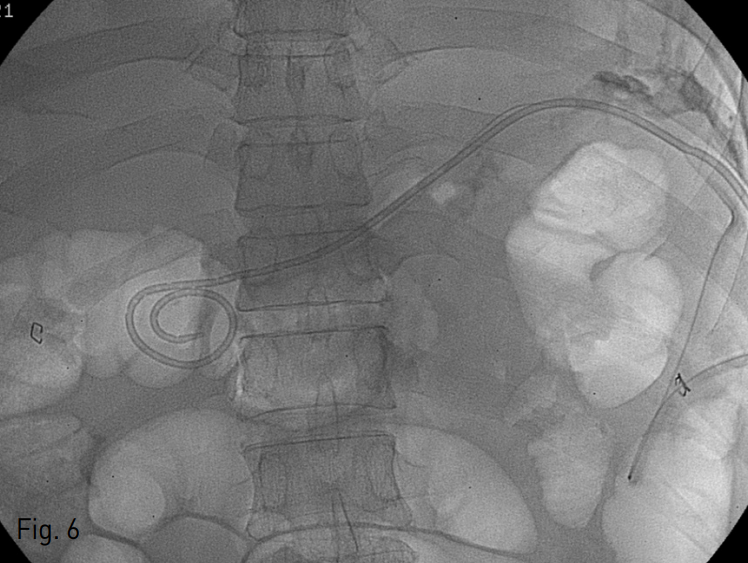

Fig. 6

8.5 Fr multi-sidehole biliary drainage catheter (Cook, Bloomington, IN, USA) was deployed.

카테터의 U자 모양의 회전부위를 지나면서 피부 아래 공간의 경로가 최단거리이자 직선 경로가 되는 지점을 조준하여 초음파 유도하에 22 gauge Chiba needle로 카테터를 천자하였음 (Fig. 3). 그 후 조심스럽게 바늘을 뒤로 빼면서 hair wire를 초음파와 투시 유도하에 조정하여 바늘이 카테터 바깥 공간에 위치하는 지 확인하였음 (Fig. 4). 이후에 hair wire가 카테터 바깥 공간의 성숙 경로 (maturated tract)를 따라 진입시키고 yellow sheath로 교체하여 조영제를 주입하였을 때 액체 저류가 조영되는 것이 보임 (Fig. 5). 0.035 inch hydrophilic guidewire를 진입시킨 후 8.5 Fr multi-sidehole biliary drainage catheter (Cook, Bloomington, IN, USA)를 거치하였음 (Fig. 6). 이후 50cc 정도의 냄새가 나는 연노란색의 농이 배액되어, 카테터를 배액용기에 연결한 후 시술을 종료함.